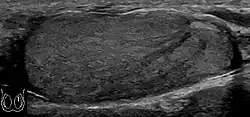

-

Doppler ultrasound of epididymitis, seen as a substantial increase in blood flow in the left epididymis (top image), while it is normal in the right (bottom image). The thickness of the epididymis (between yellow crosses) is only slightly increased (7 mm). -

Doppler ultrasound of the scrotum of the same case, in the axial plane, showing orchitis (as part of epididymo-orchitis) as hypoechogenic and slightly heterogenic left testicular tissue (right in image), with an increased blood flow. There is also swelling of peritesticular tissue.